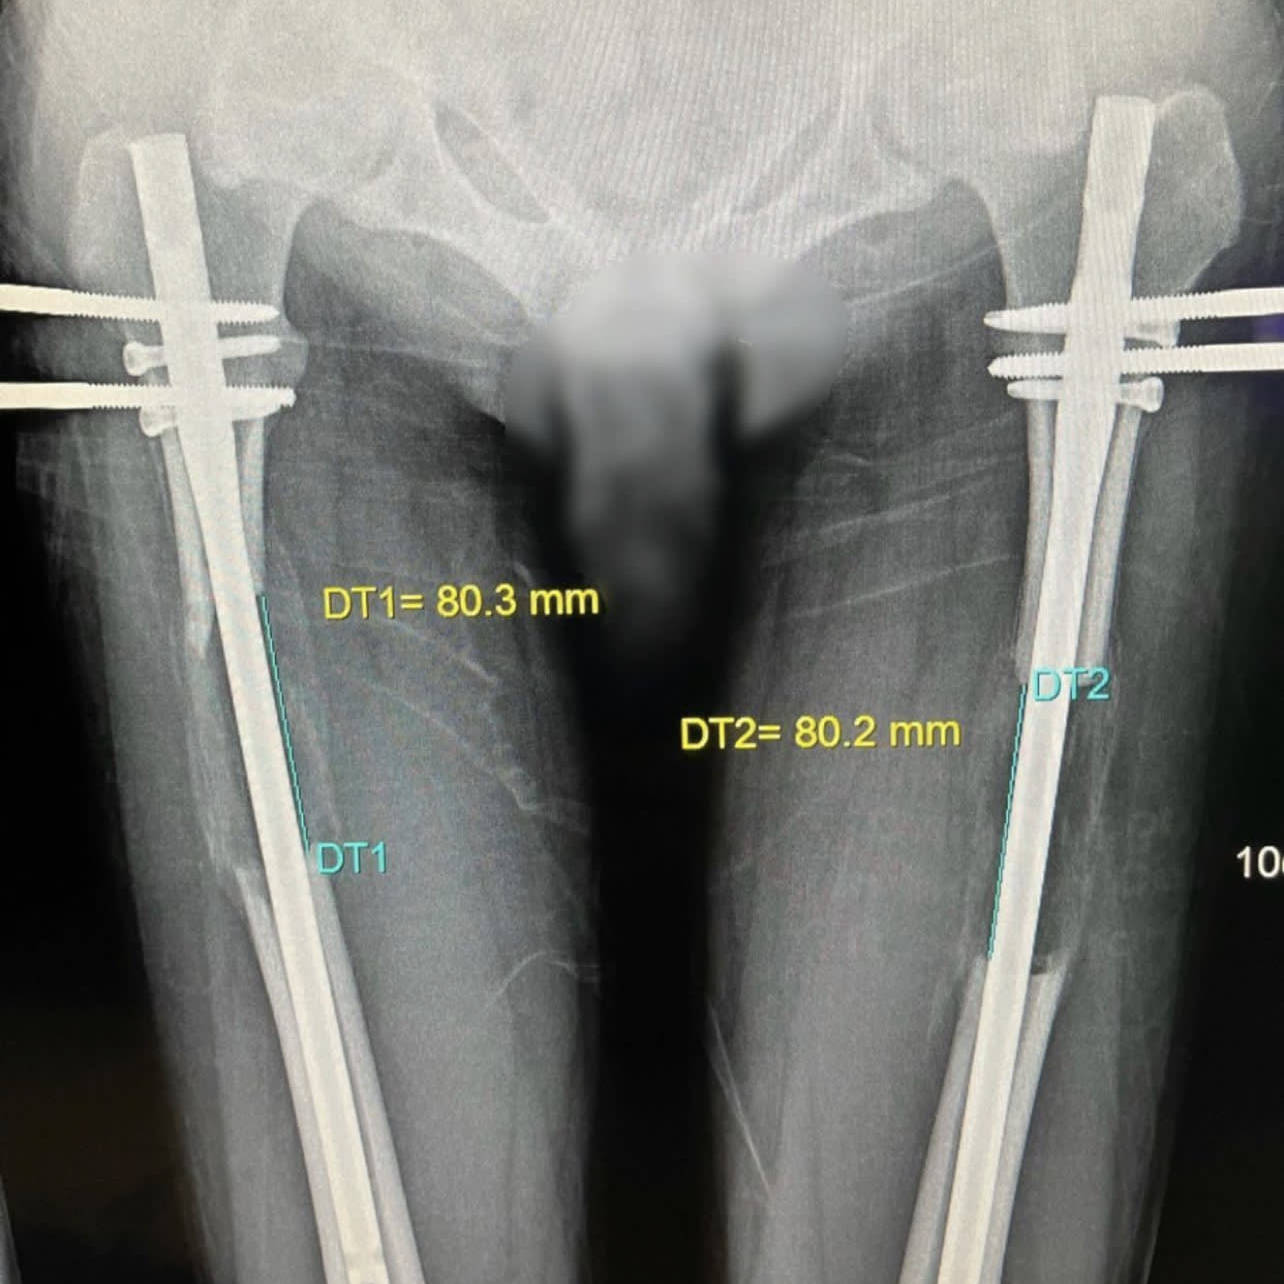

股骨肢体延长手术动画